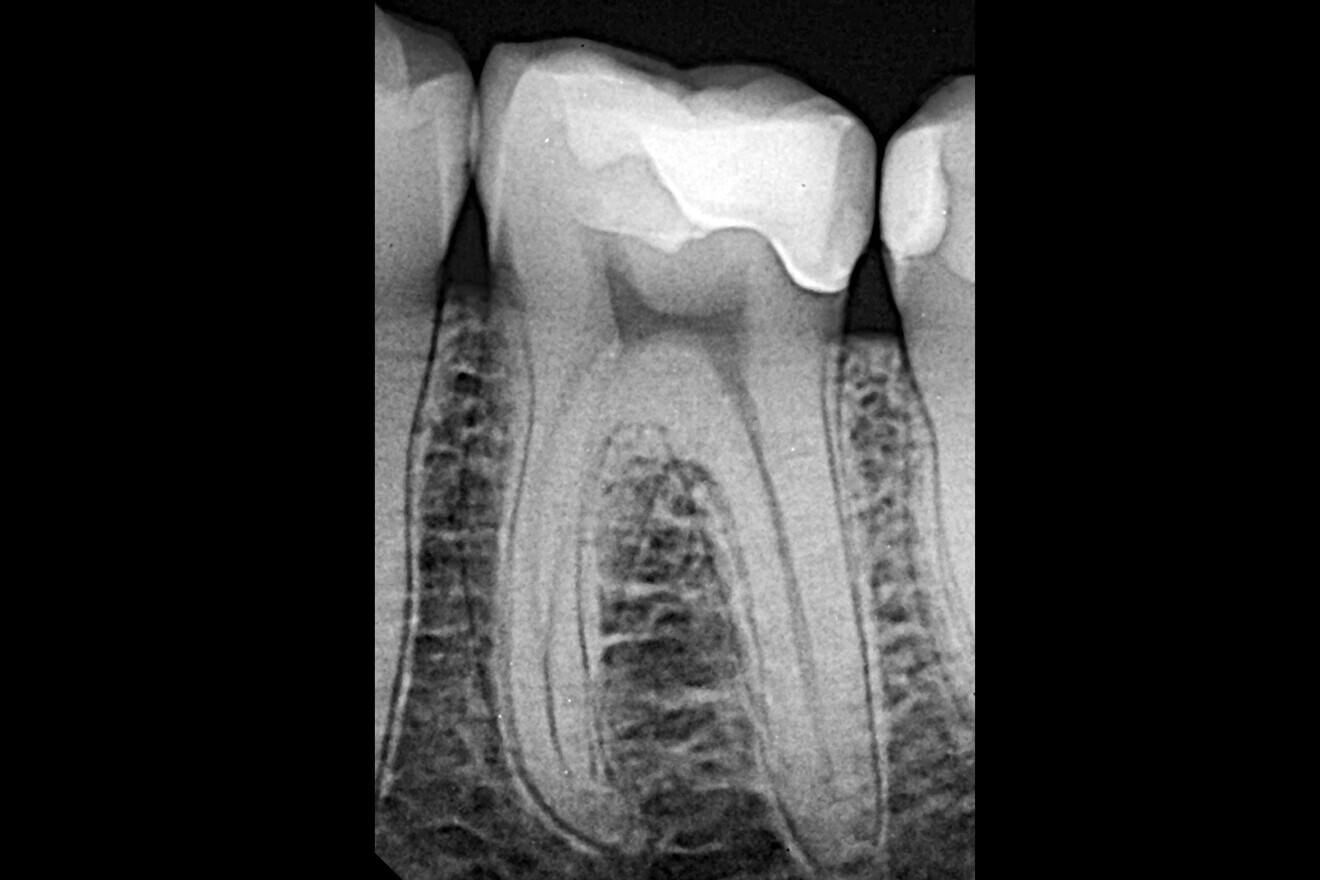

Fig. 2: Panoramic radiograph showing a distal carious lesion.

Treatment focused on a mandibular first molar with existing Class I and V composite restorations (Fig. 1). The tooth was asymptomatic, and cold testing revealed a normal response. A distal carious lesion, which was not clinically visible, was first suspected during routine screening and its extent clearly identified on the panoramic radiograph (Fig. 2).